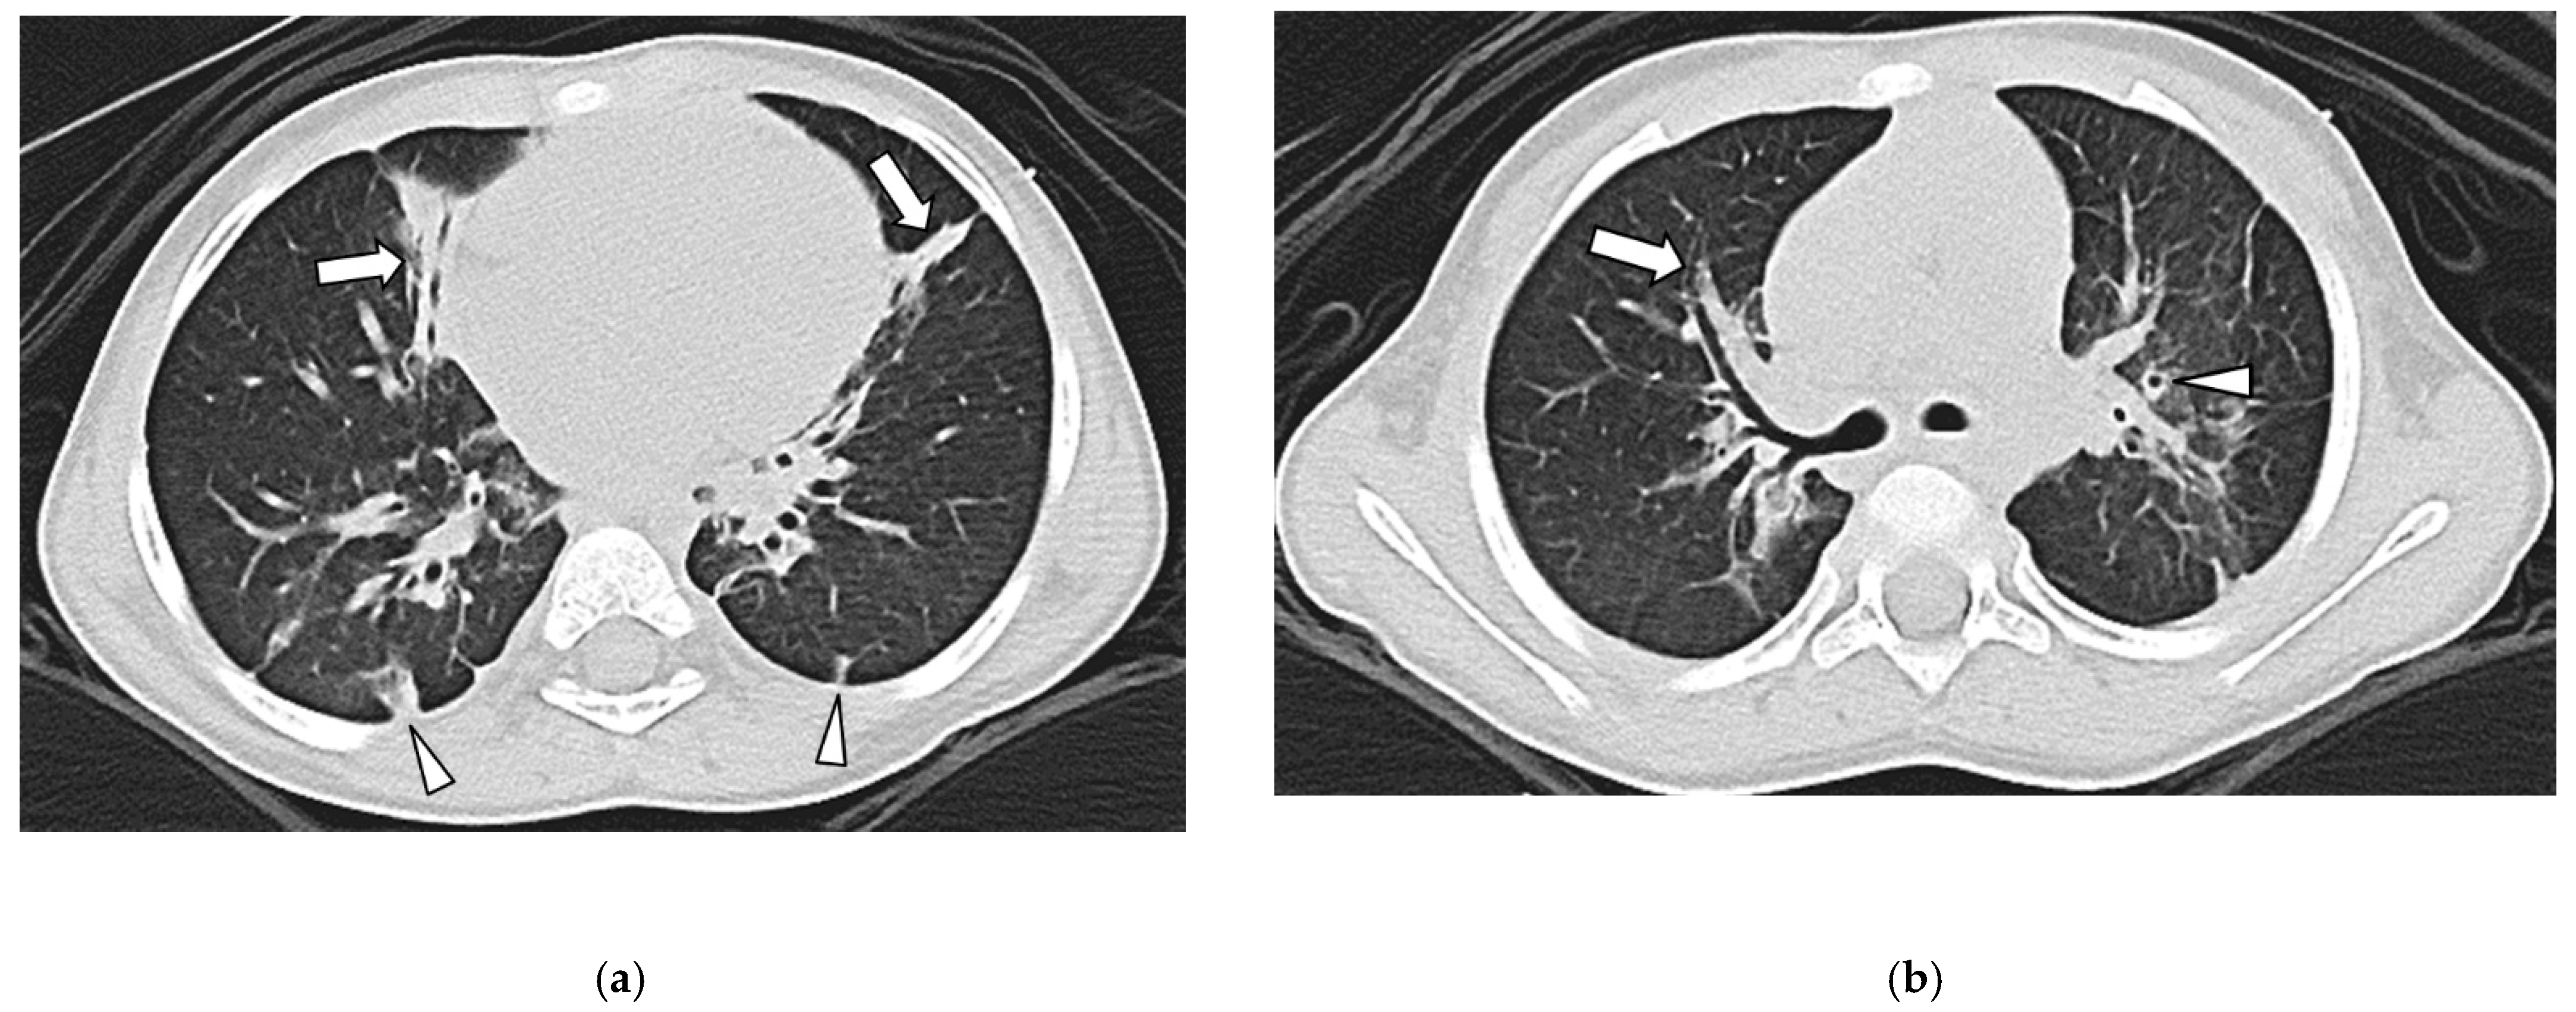

3.3. Lung Findings

3.4. Airway Findings

3.5. Pleural Findings

3.6. Interobserver Agreement

| Septal Thickening | 39/49 (76%) | 0/54 (0%) | <0.001 |

| Bronchial Wall Thickening | 0/49 (0%) | 33/54 (61%) | <0.001 |

| Bronchiectasis | 0/49 (0%) | 30/54 (56%) | <0.001 |

| Pleural Thickening | 44/49 (90%) | 2/54 (4%) | <0.001 |